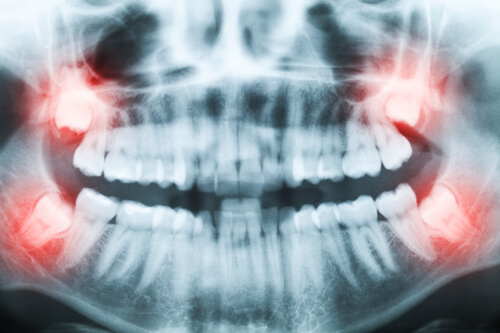

親知らず治療

親知らずがむし歯である。またはその隣の歯との間がむし歯である。どうしても奥なので歯ブラシが届きにくい場所ではあるのでむし歯になりやすい傾向になります。むし歯が進行すれば当然痛みを伴うため抜歯が必要です。

親知らずが噛んだ時に痛い先述のように磨きにくいため歯周病が進行しやすくグラグラになると噛んで痛みを伴います。